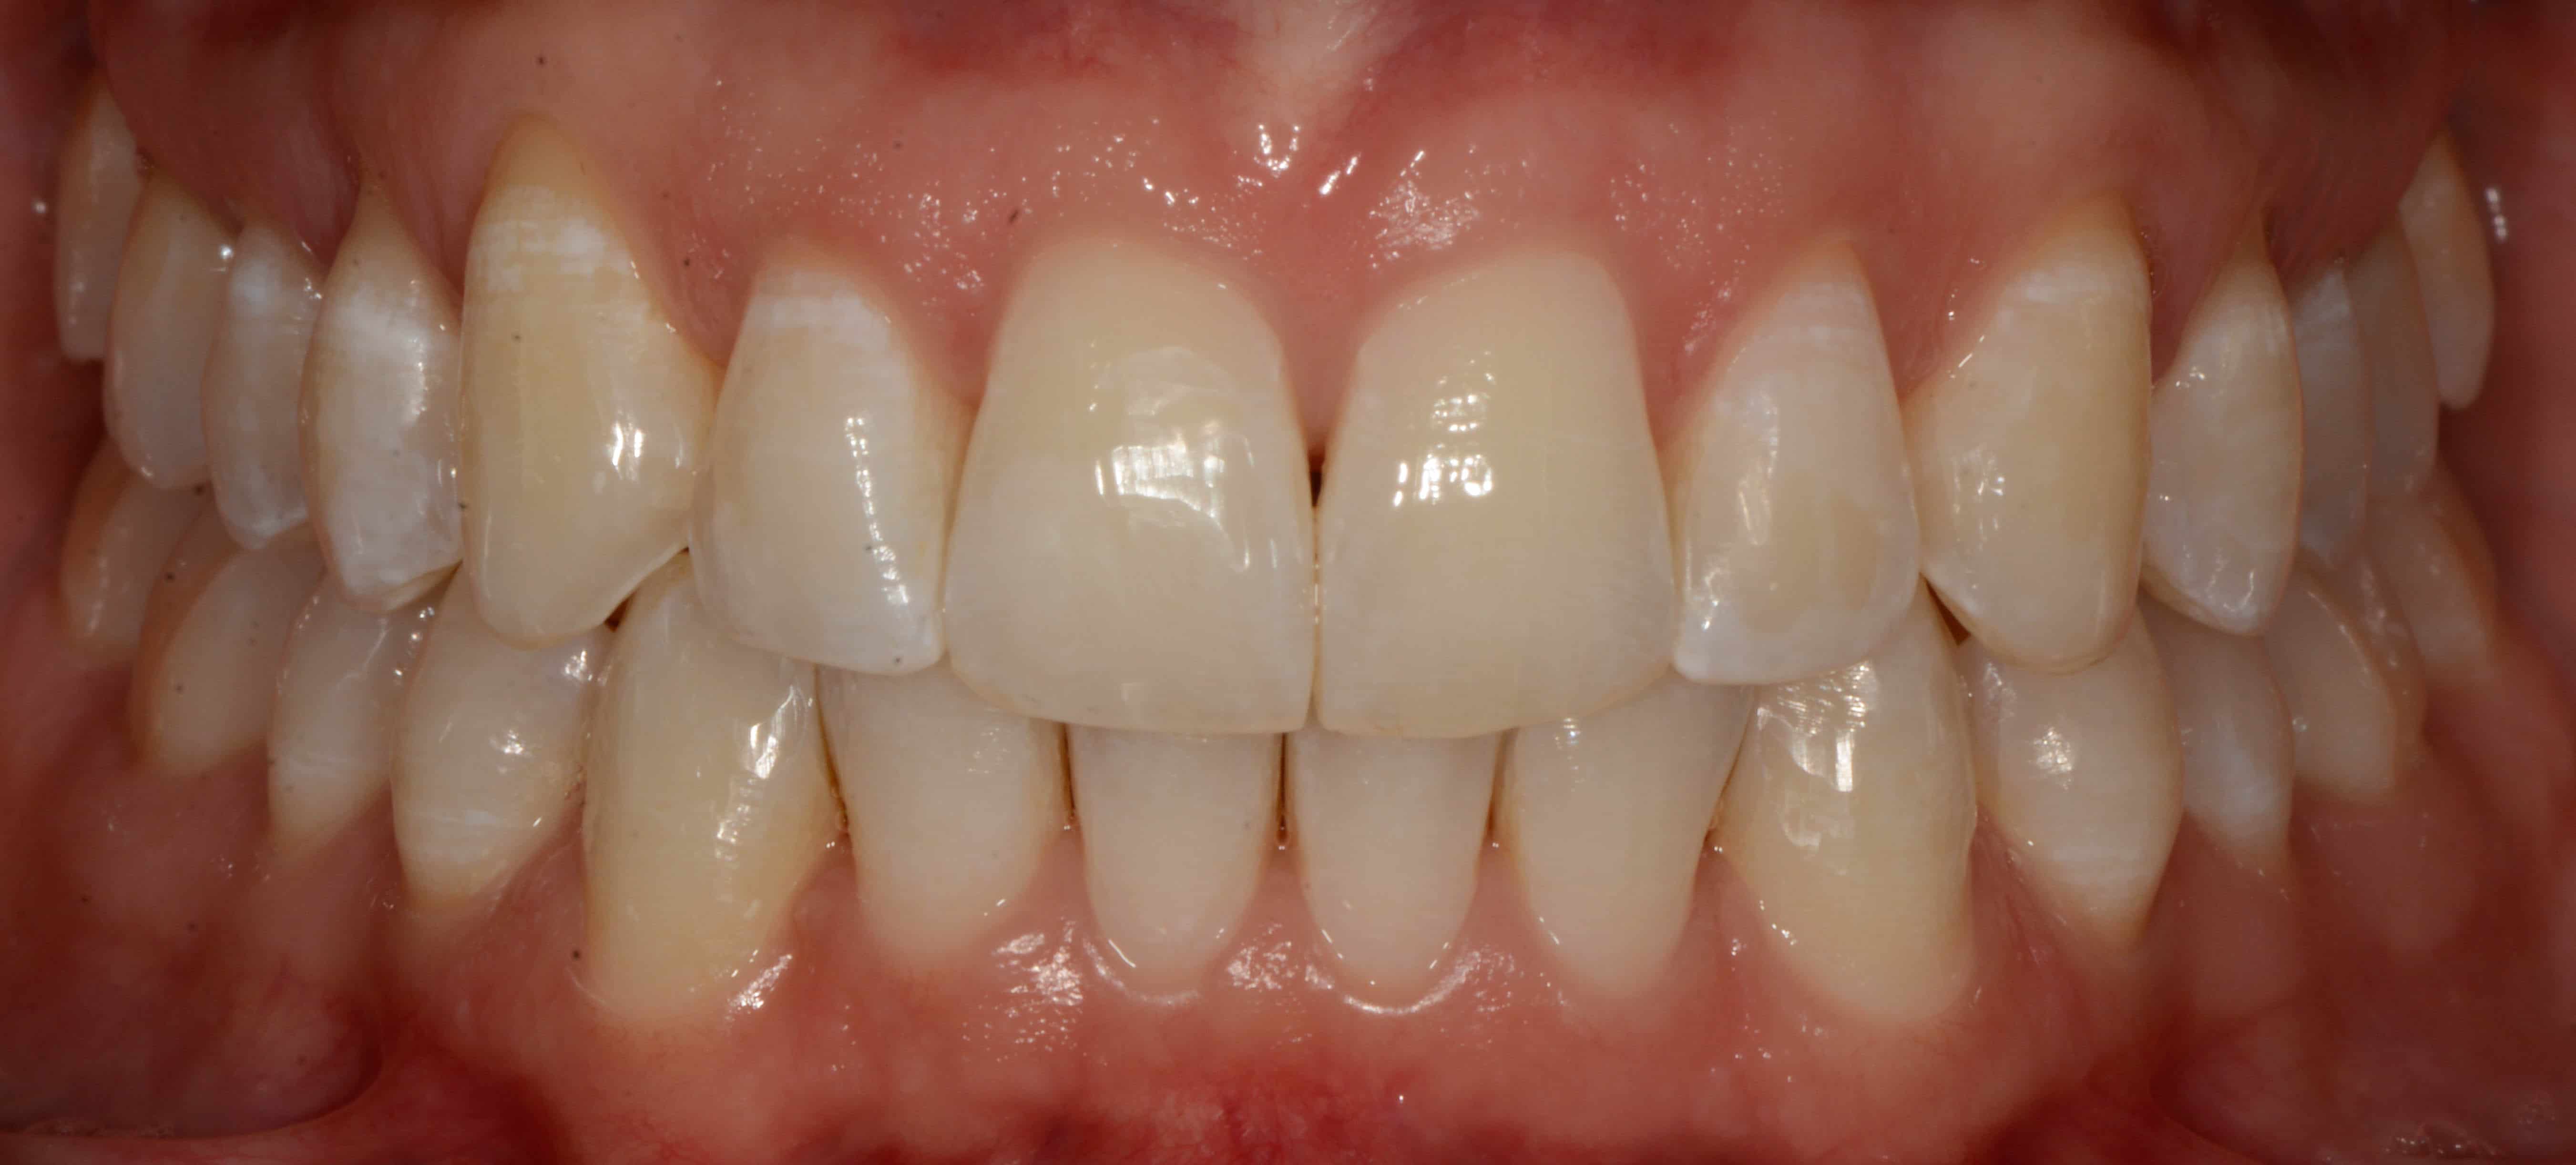

Cas #2 – retraitement avec des gouttières d’alignement